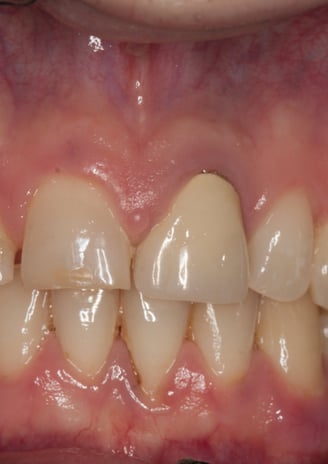

Un paziente si è presentato alla nostra attenzione con un problema di decementazione ripetuta della corona su un incisivo centrale superiore (dente 21). Oltre all'evidente instabilità protesica, la corona mostrava una discrepanza estetica marcata rispetto ai denti naturali adiacenti, compromettendo l'armonia del sorriso.

Corona incongrua: non solo non si armonizzava con i denti circostanti, ma risultava anche inadeguata dal punto di vista funzionale.

Corona Incongrua

Condizioni Iniziali